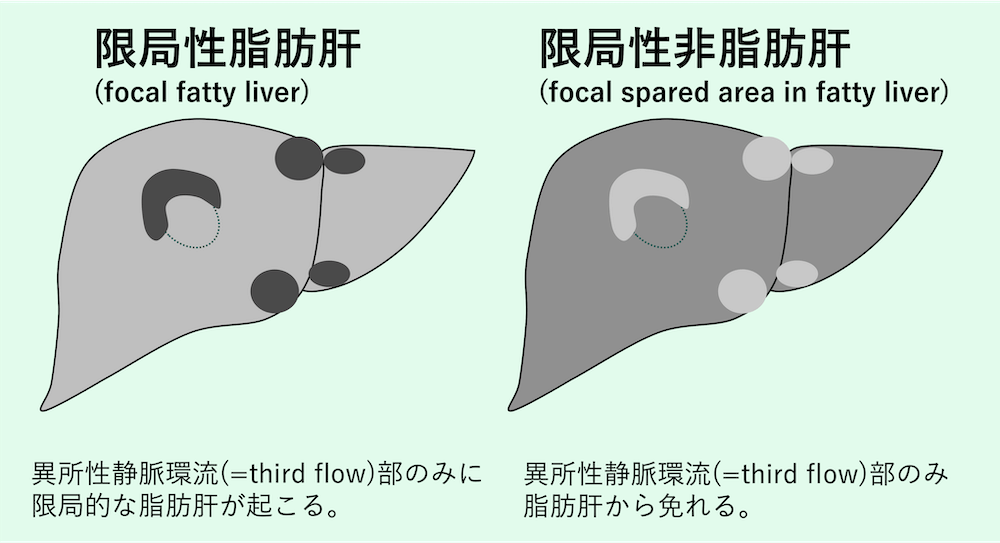

肝臓の画像診断において、腫瘍性病変と紛らわしい所見として頻繁に遭遇するのが、限局性脂肪肝(focal fatty liver / focal fatty infiltration)と限局性非脂肪肝(focal spared area)である。

これらは病的な腫瘍ではなく、血流動態の異常などに起因する局所的な変化であり、その特徴を正しく理解することは不要な精密検査や生検を避ける上で極めて重要である。

third inflowの灌流領域では、正常な門脈血とは栄養状態やインスリン濃度が異なるため、局所的に脂肪化が進展したり(限局性脂肪肝)、逆に脂肪化が免れたり(限局性非脂肪肝)する現象が生じる。主な流入経路と好発部位は以下の通りである。